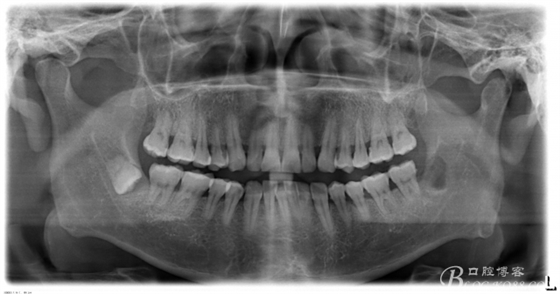

口內(nèi):38未萌出。37遠(yuǎn)中牙周袋10mm,CT:38牙冠倒置。牙齦紅腫,捫診可有少量血性滲出,無波動(dòng)感。印象診斷:38冠周炎。處理:1.抗炎治療,改善張口度。2.炎癥消退后,拔除38.

一、術(shù)前CBCT影像資料

圖13.術(shù)后的全景片影像